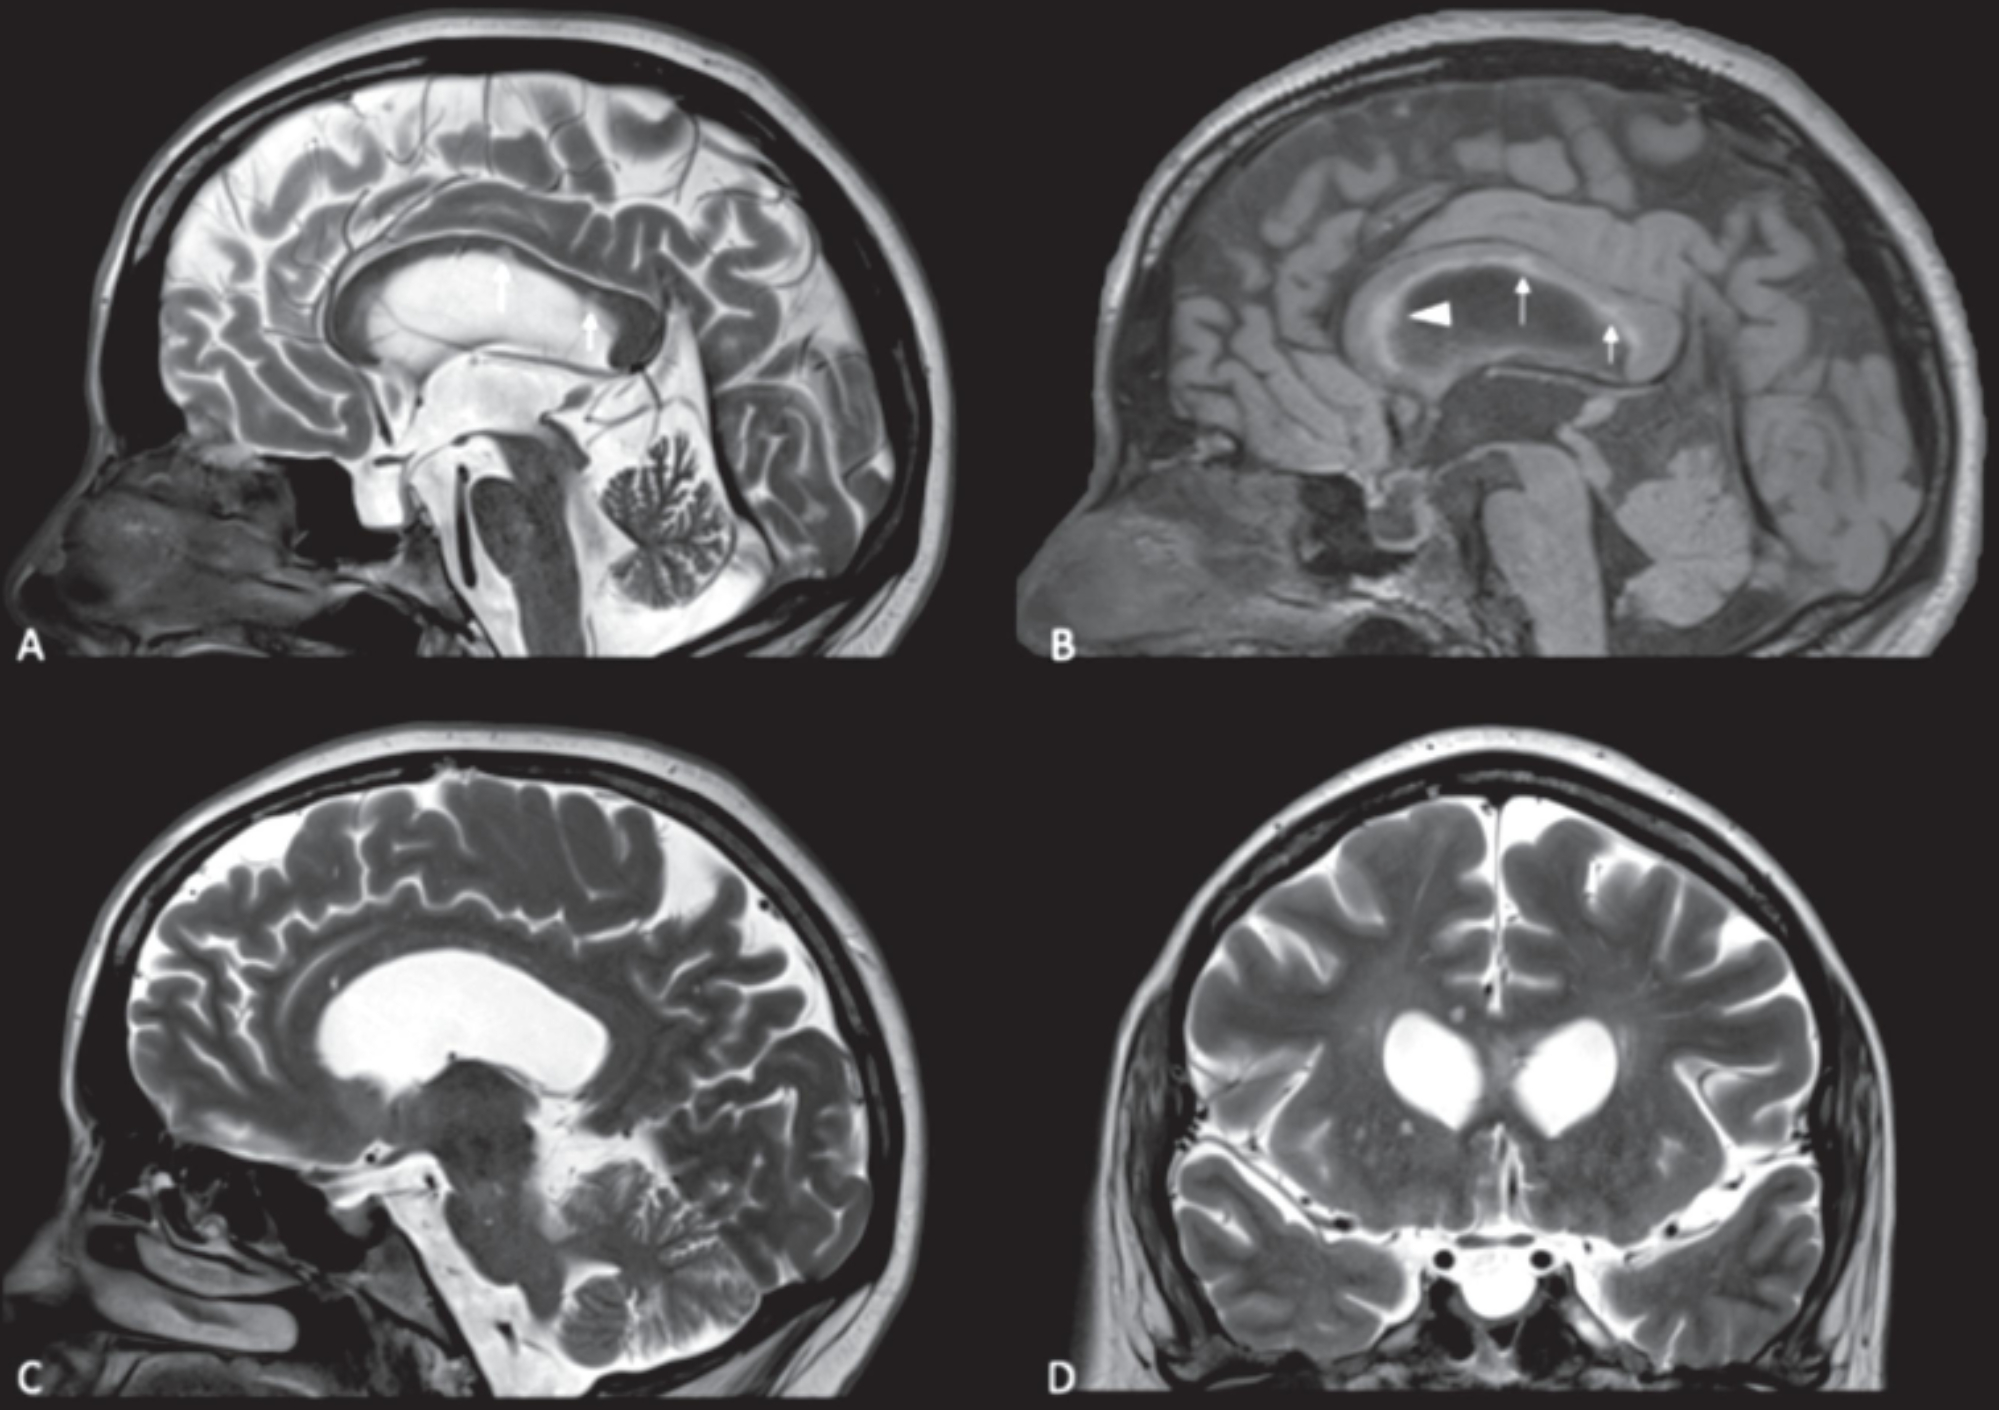

Según el portal Orphanet, este síndrome "clínicamente, está caracterizado por la tríada de encefalopatía (trastornos cognitivos y de conducta, cambios de personalidad, psicosis, cefalea) y/o disfunción focal del SNC, disfunción visual"

Cabe recalcar que el desconocimiento de esta afección hace muy difícil su diagnóstico y, por ende, su respectivo tratamiento. Sin embargo, a diferencia de otras enfermedades, se pueden realizar maniobras para mejorar la calidad de vida del paciente.